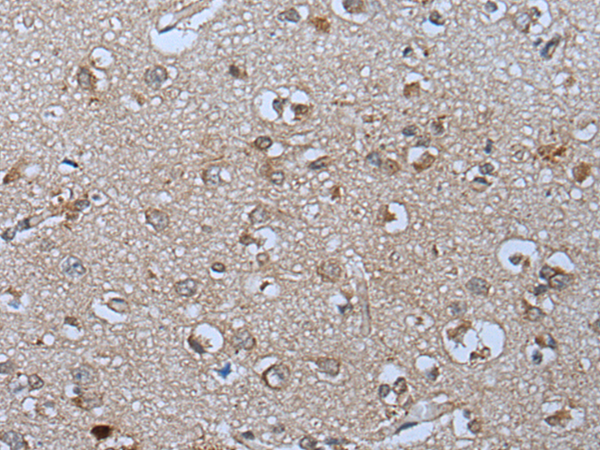

分类: 科研抗体货号: P05990别名: XT1; XTI; XT-I; DBQD2; XYLTI; PXYLT1; xylT-I应用: WB,IHC反应种属: Human, Mouse, Rat